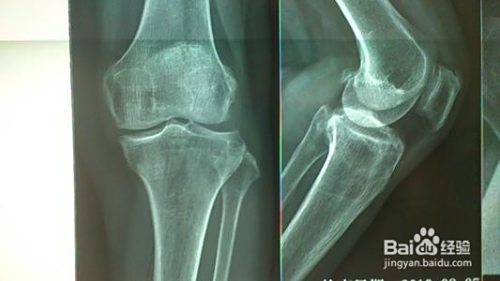

身体原因——若是是时候累积痛苦悲伤影响或者因为其他不测导致,建议去病院做具体的查抄,拍X光片,清晰地找到问题地点,需要时改换膝盖。